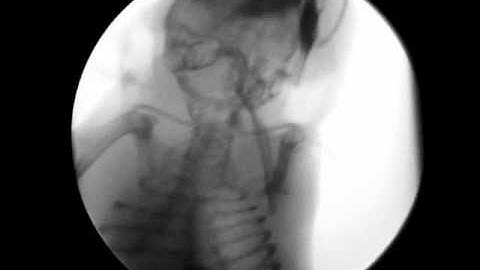

Fluoroscopic video of mouse II, see insides of mouse as it moves around, x-ray